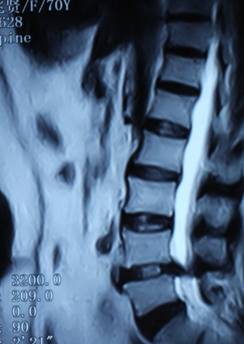

2. 患者董某,女,70岁,因“腰部疼痛并右下肢疼痛、麻木1年余,加重10天”入院。入院前曾多次行针灸、理疗、骶管封闭等治疗,经治疗后病情复发。入院见患者腰痛并右下肢疼痛,双足麻木,间歇性跛行,跛行距离约50米。查:直腿抬高试验右30°阳性,右踇背伸肌力、腓骨长短肌肌力Ⅲ级,双小腿外侧、足背皮肤感觉减退,右侧为甚。入院后诊断为腰椎间盘突出症。患者既往患高血压、冠心病、慢性胆囊炎、胆结石病史,形体肥胖。入院后完善检查,明确诊断,请相关科室会诊后认为手术风险大且患者形体肥胖,为手术增加难度,势必延长手术时间,增加手术风险。经科室讨论后行经皮椎间孔镜下髓核摘除,手术麻醉方式为局麻。入院后第三日手术,经椎间孔入路椎间孔镜下髓核摘除椎管扩大成形术。手术顺利,术中无出血,手术时间约1小时。术中可与患者交流。术后患者即可感右下肢无疼痛,第二天佩戴腰围下地活动后双下肢无不适。术后第三天出院,术后第三天复查腰椎MRI示突出髓核已摘除,神经根无受压。术后随访三月,患者目前病情恢复良好,无下肢疼痛。

术前患者腰椎MRI